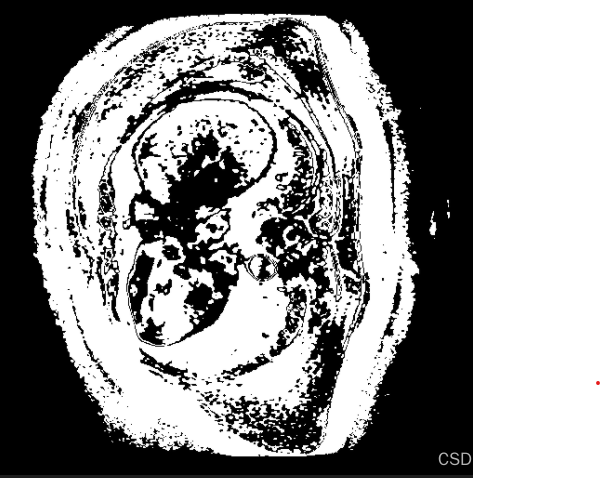

使用网上的大多数格式转换过来图像失真过于严重,出现了这种情况: